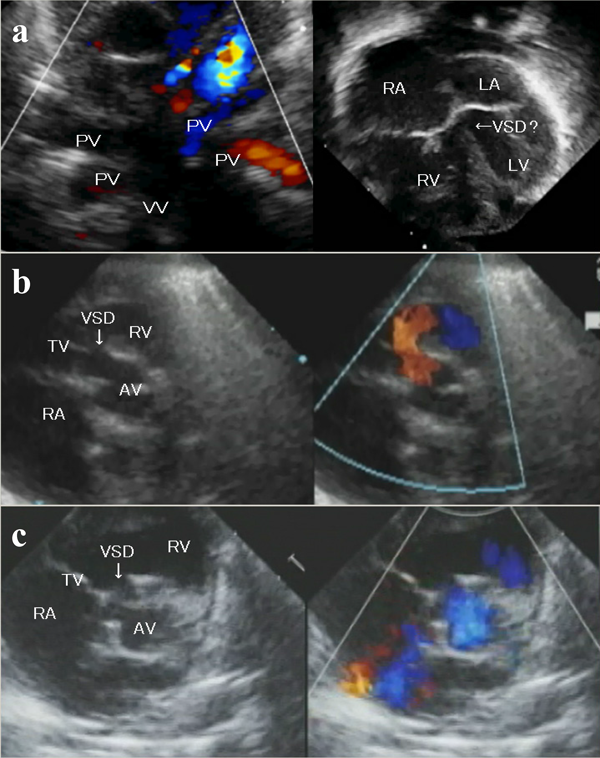

3)心臓超音波検査(Fig. 1a

心室中隔は右室側に偏位

左室拡張末期径(LVDd)13.0 mm(Z value −1.6),左室収縮末期径(LVDs)10.6 mm,三尖弁輪径(TVD)11.0 mm(−0.6),僧帽弁輪径(MVD)8.6 mm(−2.6)

ASD:二次孔欠損型,径3.1 mm,右→左shunt

PDA: 1.6 mm,両方向性血流

右上肺静脈(RUPV): 3.3 mm,右下肺静脈(RLPV): 2.0 mm,左上肺静脈(LUPV): 2.5 mm,左下肺静脈(LLPV): 2.4 mm,共通肺静脈(CPV): 8.4 mm,垂直静脈(VV): 肝静脈合流部で下大静脈に流入しており最狭窄部1.8 mm(continuous flow 1.4 m/s)

Fig. 1 Transthoracic echocardiography

a: Preoperative echocardiography in Patient 1. Echocardiography revealed an infracardiac TAPVC. Preperative pulmonary hypertension initially made it difficult to identify the VSD. b: Short axis view at the aortic valve level shows left-to-right shunting through the perimembranous VSD. c: Short axis view at the aortic valve level shows preoperative right-to-left shunting through the perimembranous VSD. TAPVC; total anomalous pulmonary venous connection, PV; pulmonary vein, VV; vertical vein, RA; right atrium, RV; right ventricle, LA; left atrium, LV; left ventricle, VSD; ventricular septal defect, TV; tricuspid valve, AV; aortic valve.

3)心臓超音波検査(Fig. 1c

LVDd 10.9 mm(Z value −2.5),LVDs 10.6 mm,TVD 8.8 mm(−5.1),MVD 9.8 mm(−2.6)

VSD: perimembranous outlet type,径4.2 mm,右→左シャント

PFO:径2.7 mm

RUPV: 3.3 mm,RLPV: 3.7 mm,LUPV: 3.5 mm,LLPV: 3.7 mm,CPV: 6.0 mm,VV:上大静脈に流入部で狭窄あり(連続性血流・平均血流速1.6 m/s)